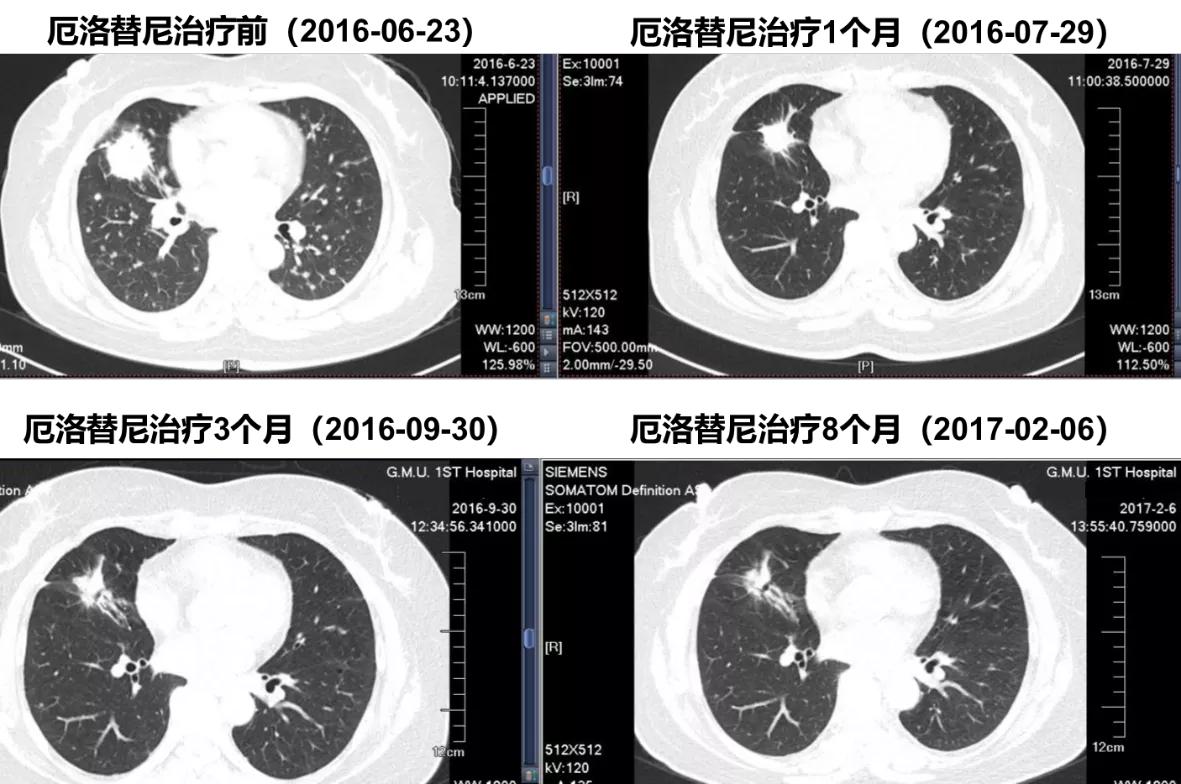

厄洛替尼一线治疗患者CT随访

胸部CT显示:右中肺靶病灶最佳疗效PR。

胸部CT显示:在2018.04.03右中肺靶病灶略增大,5.25 CT示持续增大。